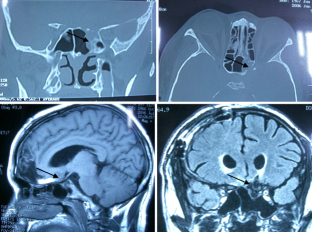

Fig.1